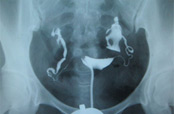

选择性输卵管无痛造影

意义:检查输卵管通畅度、子宫形态

怎么查:用导管注入造影剂的反应,判断女性输卵管是否正常

查多久:30分钟

必要性了解输卵管的通畅性极准,必查